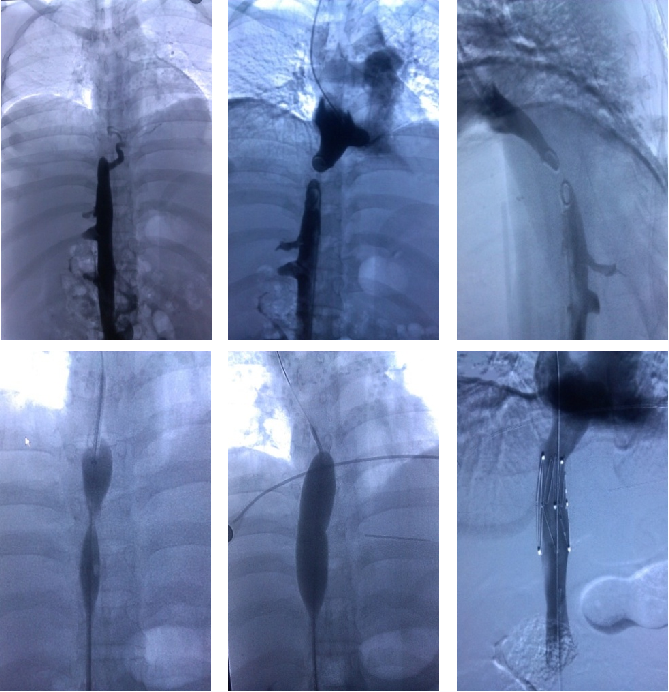

血管支架植入术治疗Budd-Chiari综合征